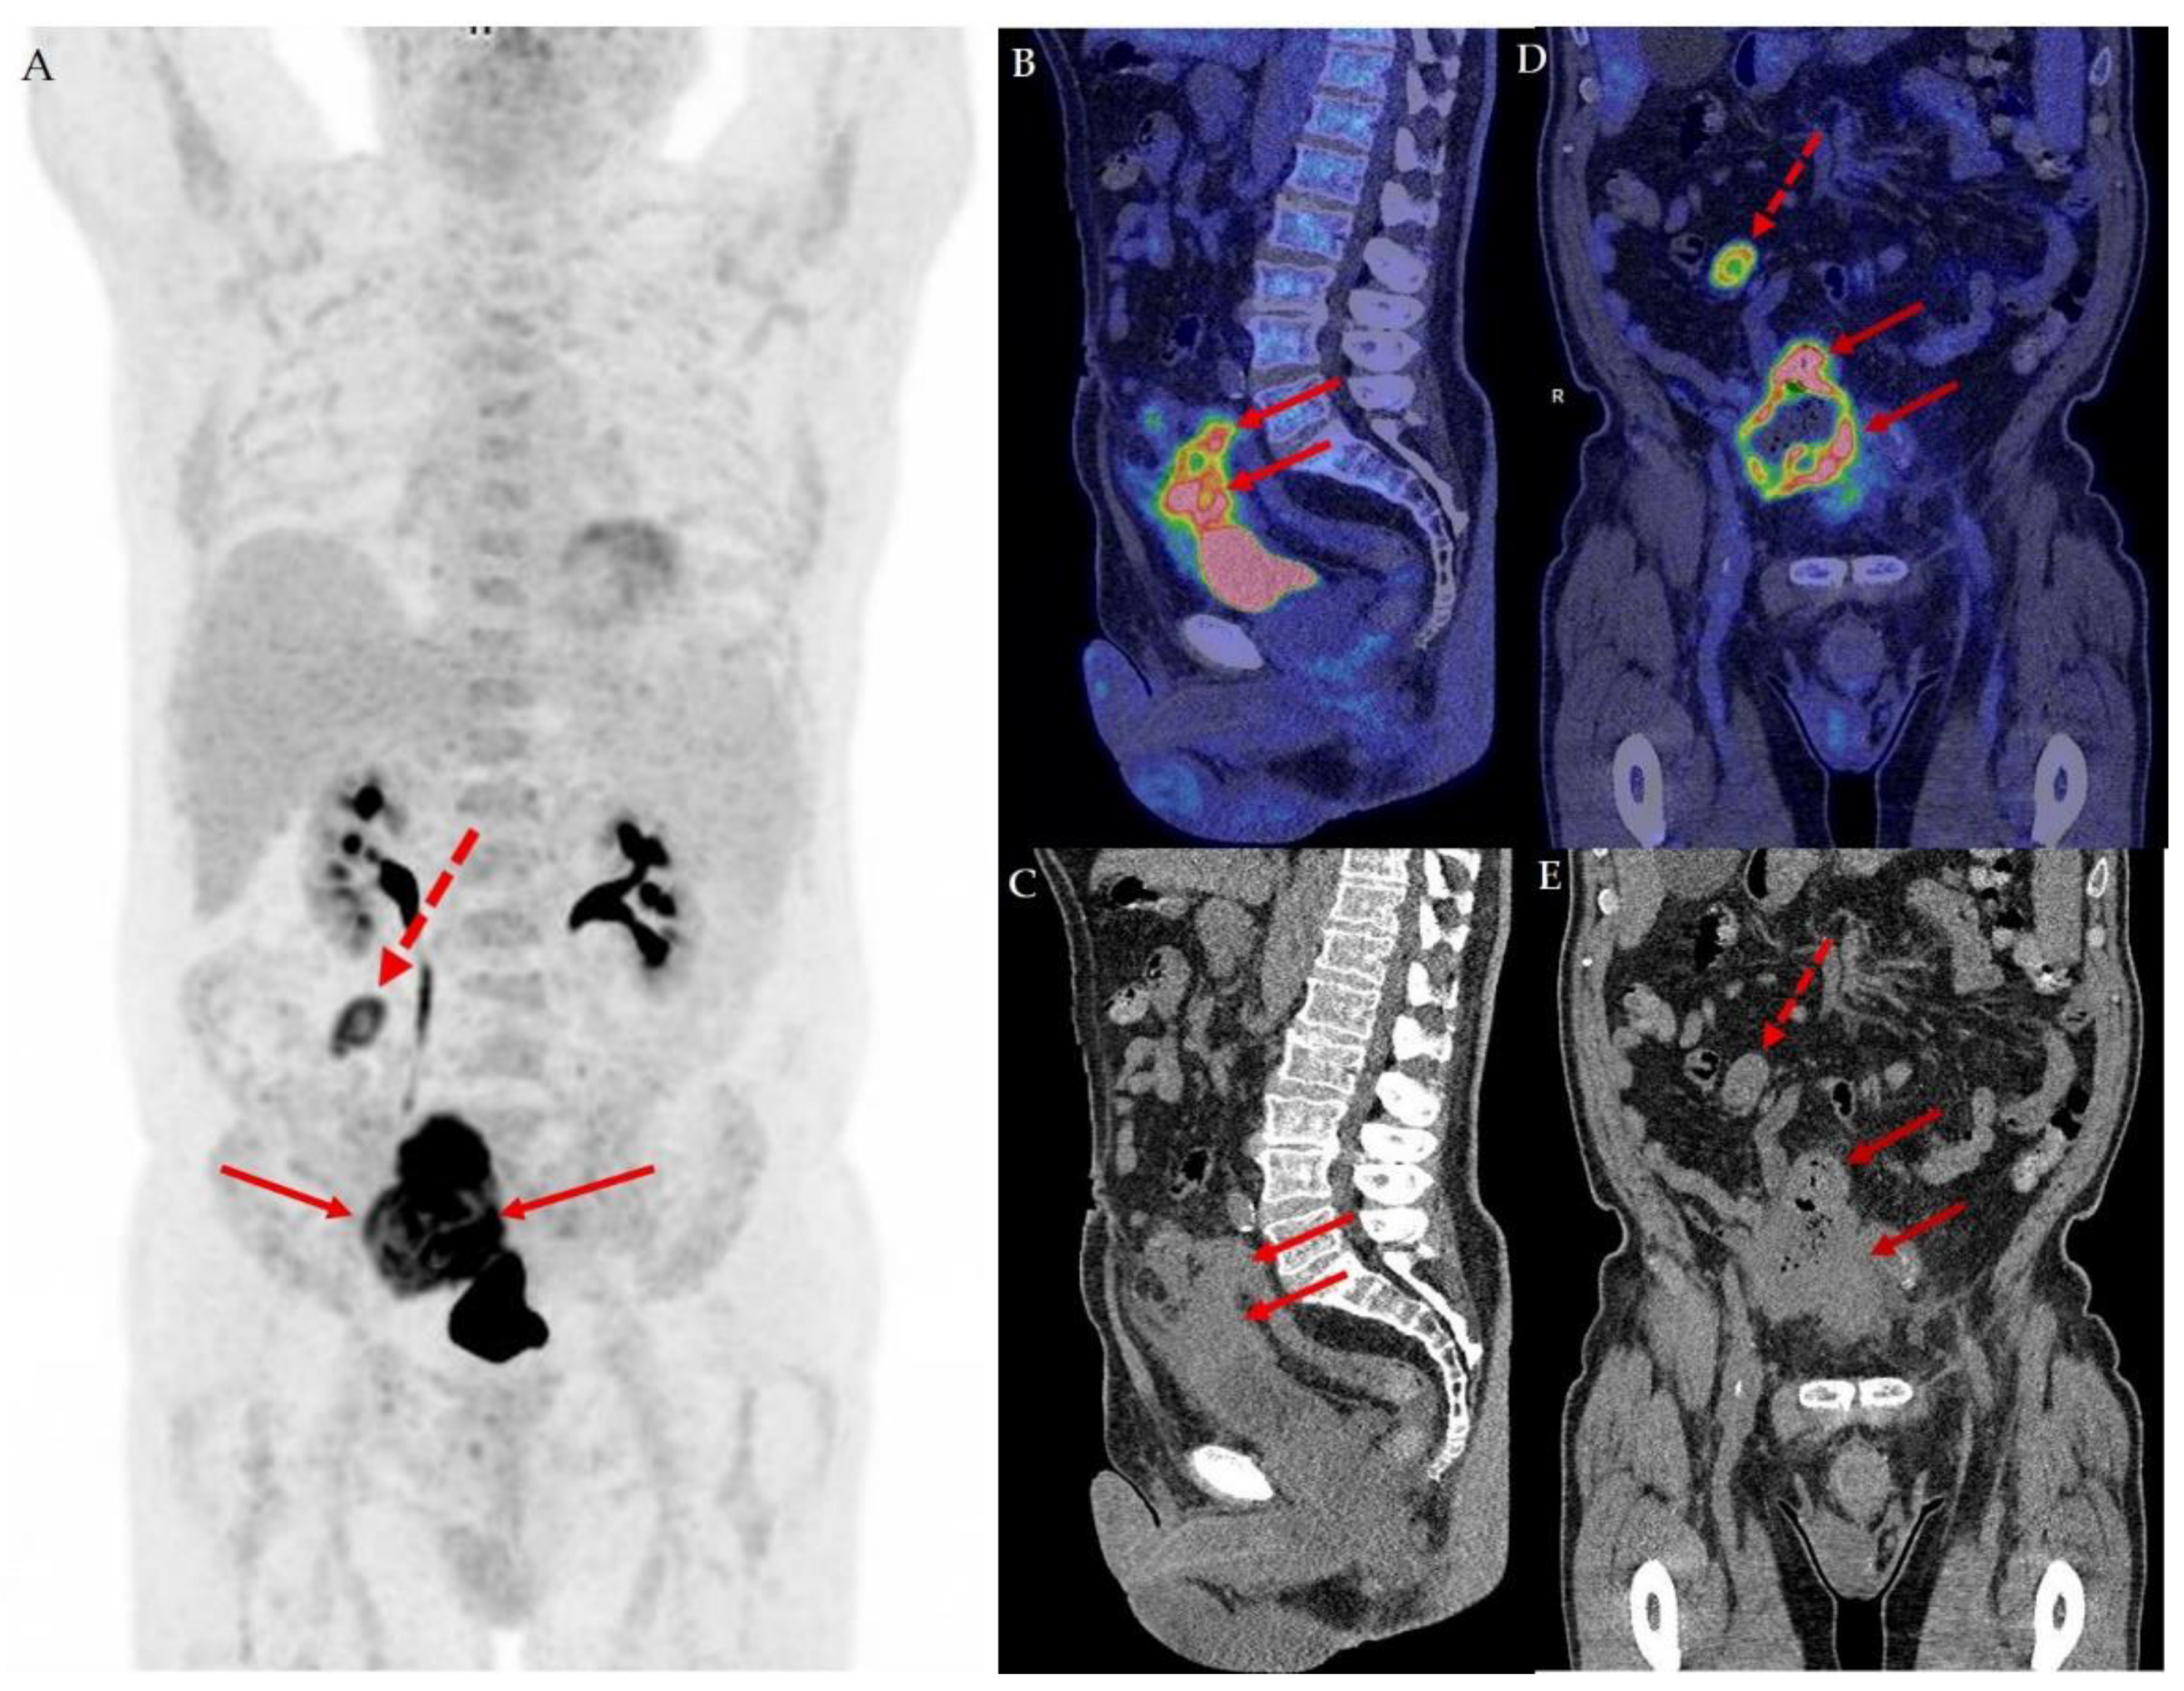

18F-FDG PET/CT in a Case of Urothelial Carcinoma in the Urachus Presenting as Colon Cancer